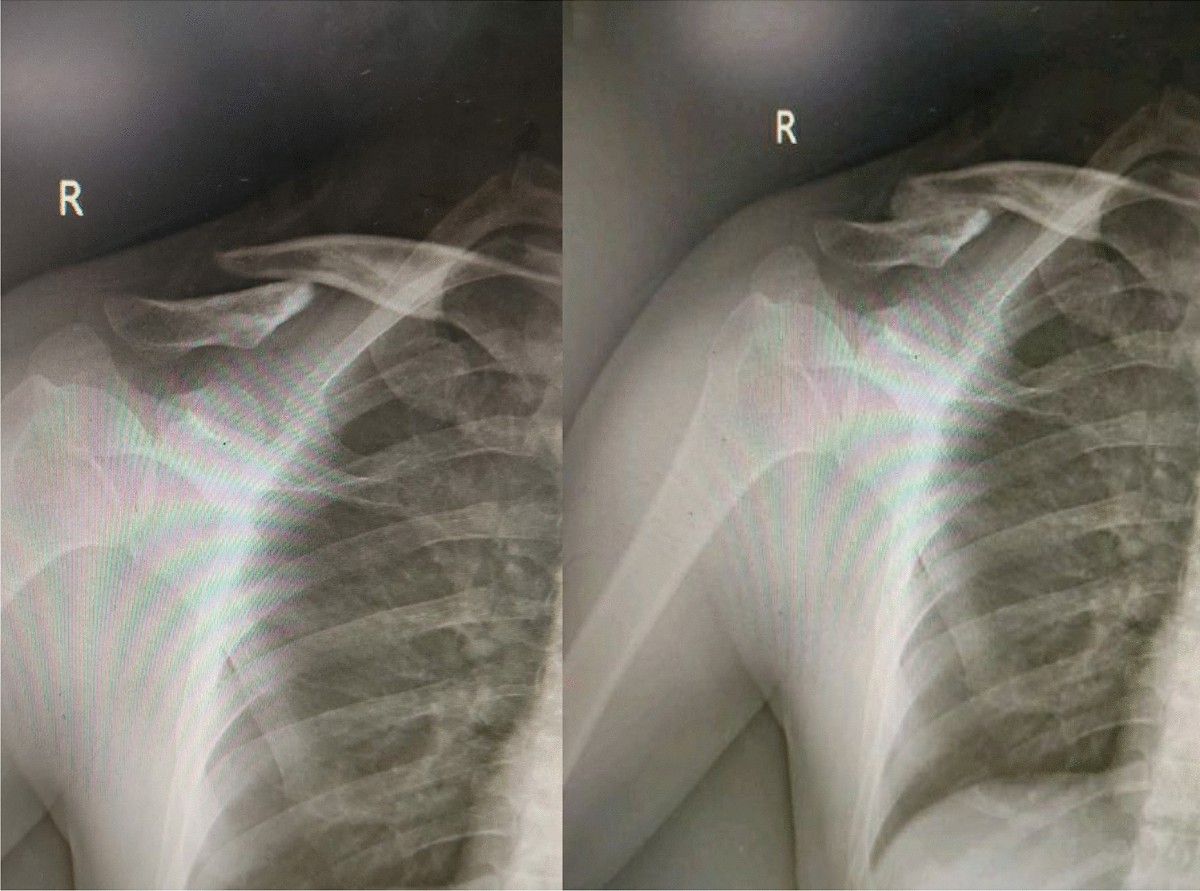

Clavicle fractures : The Shoulder and Elbow Clinic

Clavicle Fractures, symptoms, types, diagnosis and treatment with surgery and without surgery.